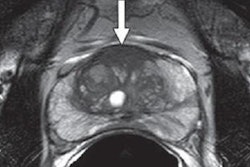

MRI-targeted biopsies combine MR images of suspected cancer with real-time ultrasound. In the new study, the technique discovered approximately 10% more prostate cancers than systematic biopsy alone and upgraded or changed 22% of more than 2,100 cases to a more aggressive forms of the disease, according to researchers from the U.S. National Cancer Institute (NCI).

Pinto and several NIH colleagues first developed MRI-targeted biopsies more than 10 years ago, and they worked with Philips Healthcare to develop software designed to overlay MR images onto ultrasound in real-time to provide a view of lesions from which samples could be taken. It was a task not possible solely with systematic biopsy, which is a considerably less direct method of locating and sampling suspected cancerous lesions and naturally is prone to miss more severe cancer.